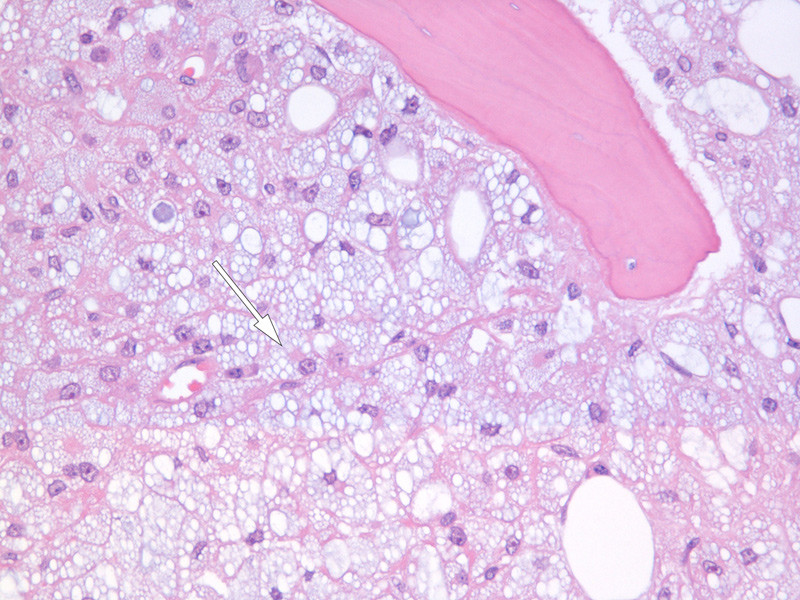

Initial evaluation of the bone marrow smear revealed a hypoplastic, fatty marrow with abundant vacuolated macrophages, known as foam cells (Fig. 1). There was erythroid and myeloid dysplasia, but no elevation of blast count. The bone marrow biopsy showed massive infiltration of macrophages, and hypoplastic haematopoiesis (Fig. 2). The macrophages contained vacuoles of somewhat varying size.

Figure 2  Light micrograph of bone marrow biopsy stained with haematoxylin and eosin (HE). The image is dominated by tightly…

Figure 2 Light micrograph of bone marrow biopsy stained with haematoxylin and eosin (HE). The image is dominated by tightly packed macrophages containing vacuoles of varying sizes with a bluish-grey colour typical of polyvinylpyrrolidone (PVP) or povidone (arrow). In the upper right, part of a bone trabecula can be seen